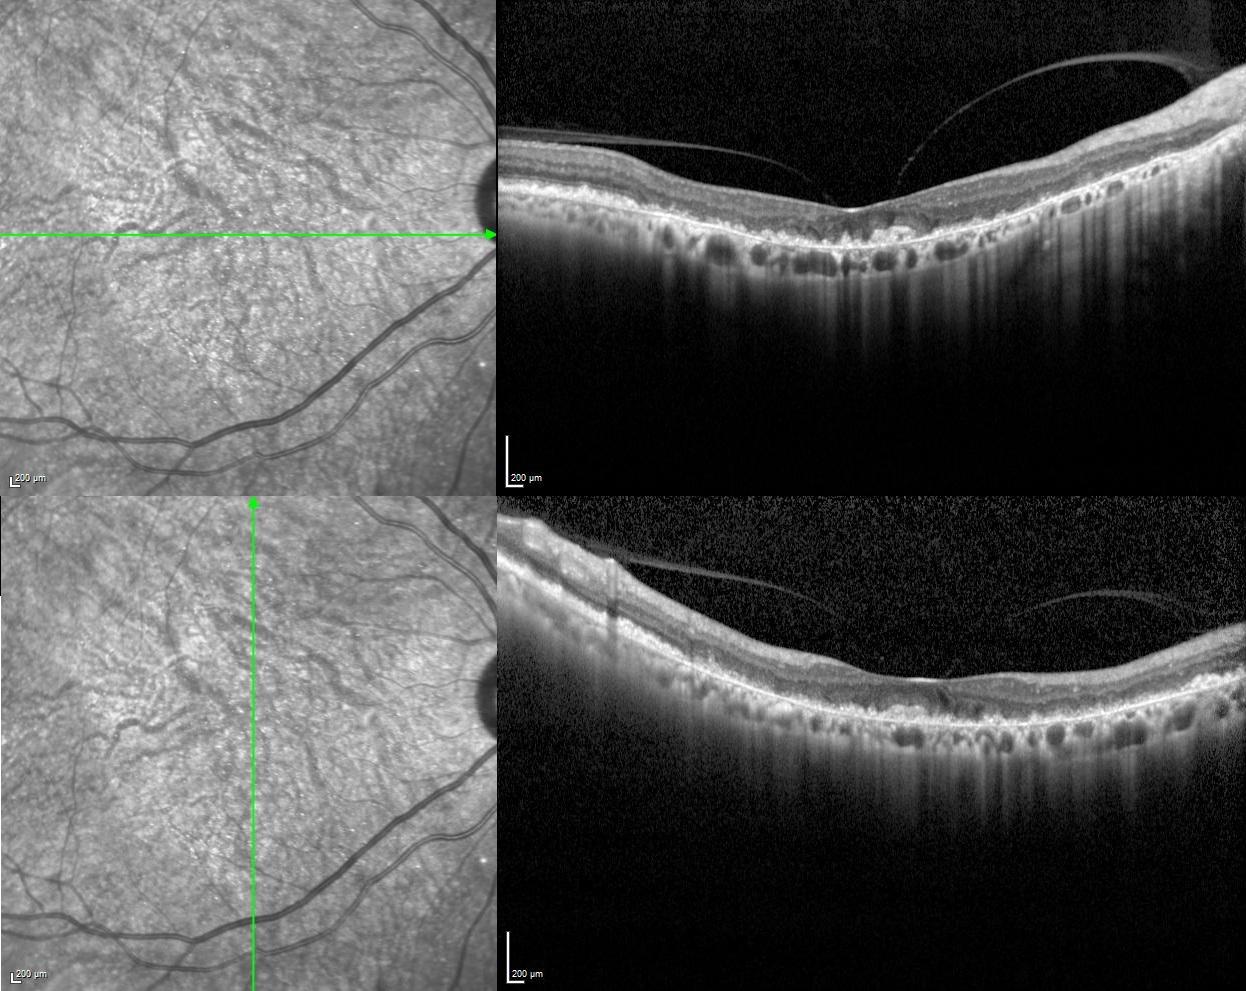

Vertical and horizontal optical coherence tomography scans revealed subretinal accumulation of drusen-like deposit in additon to outer retinal and choriocapillaris atrophy in both eyes.